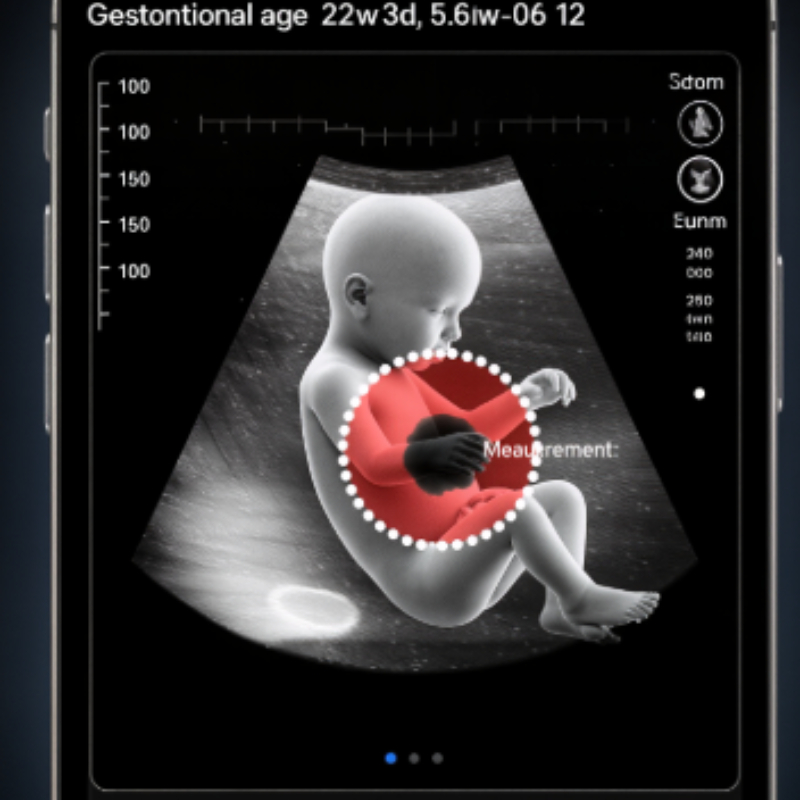

By week twenty-two, the images grew sharper, our baby more defined. The spine brightened like a sunrise, but always with that small pause—a break in the line. The surgeon who met us spoke with warmth and precision. “If the lesion is open, we’ll protect it at birth and repair early. We get better at this every year,” she said. Her smile wasn’t one that dismissed worry—it was a promise to walk beside us through it. I carried that smile home like a lantern.